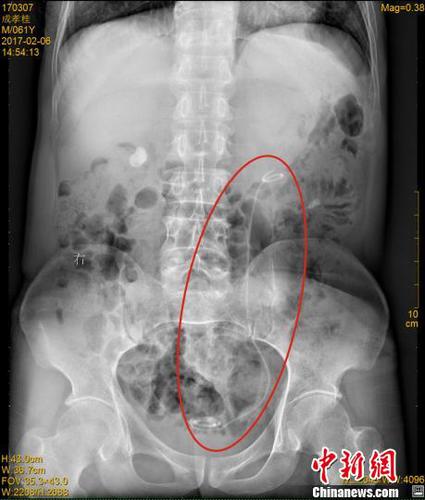

X光下,成先生体内的导管清晰可见

在医院接受B超检查时,医生发现成先生双肾均有结石、严重积水,此外,其左侧腰部还有一根条状物。在拍摄了X光片后,医生才发现,成先生体内竟然遗留着一根医用导管(双J管)。医生仔细询问后,成先生终于想起自己7年前接受过手术,这意味着这根长达30多厘米的导管,在其体内隐藏了7年时间。